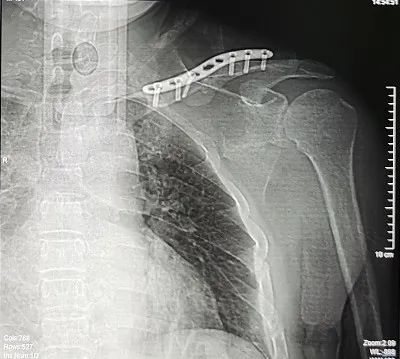

11.04,因患者左肩关节疼痛伴活动障碍,行“左锁骨骨折切复内固定术”。

手术后